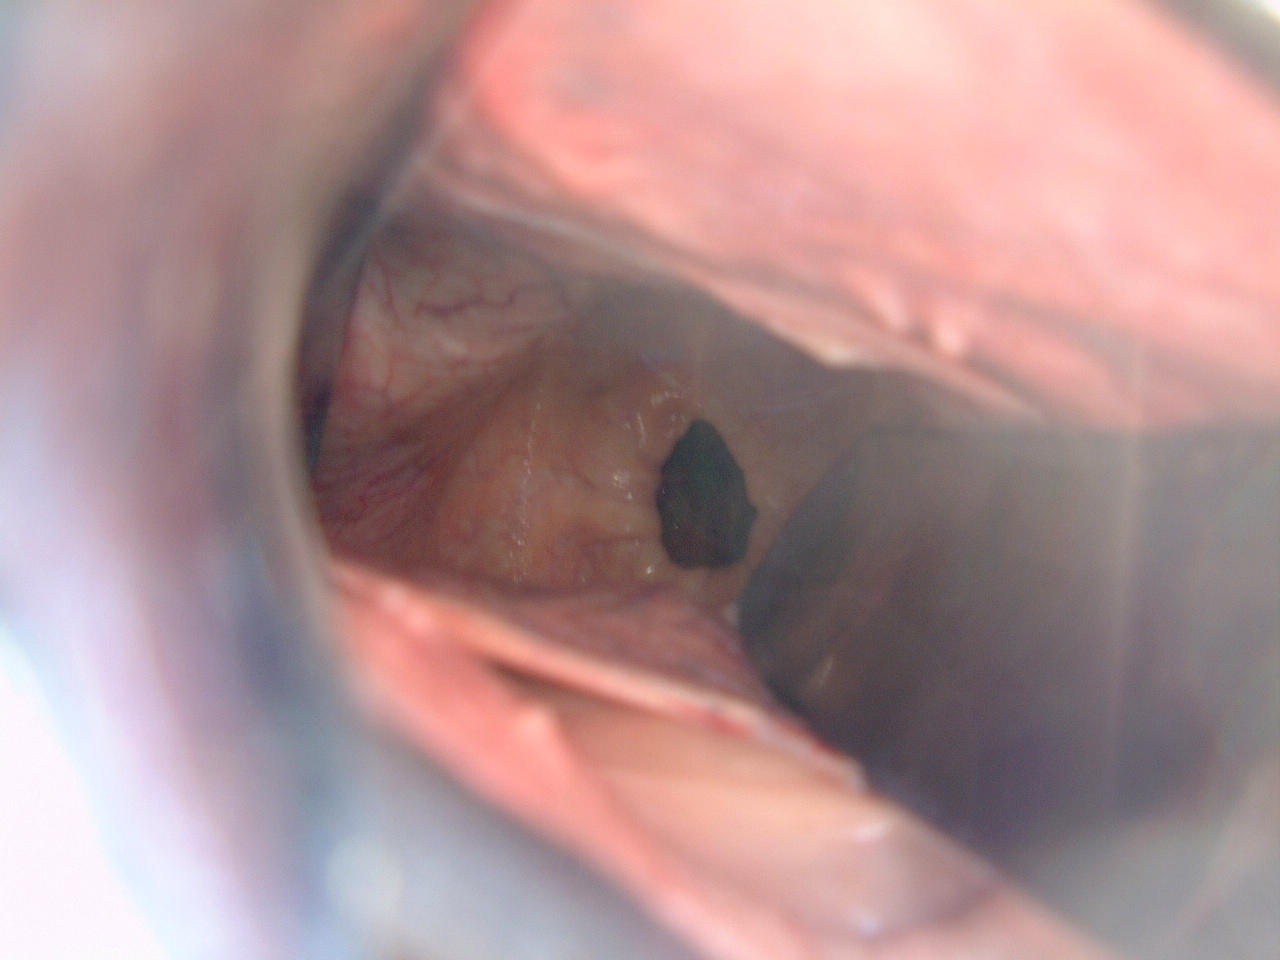

子宮頸管ポリープ「ポリープ切除術・膣ポリープ 」まりこクリニック 京都・滋賀。

子宮頸がん大阪赤十字病院がん診療センタ。